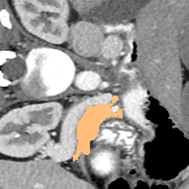

Pancreas-NIH Dataset: Pancreas-NIH dataset [11] consists of 82 3D abdominal contrast-enhanced CT scans. Following the commonly-used data split in Luo [21], we take 62 samples for training and the rest 20 samples for testing.

Some qualitative segmentation results on the three datasets are shown in Fig. 4, where we can observe that the proposed DSPIF achieves accurate segmentation results.

Results on Pancreas-NIH Dataset: The quantitative results on the Pancreas-NIH dataset are shown in Tab. 2. Under the setting of using 10% labeled images, the proposed DSPIF achieves consistent improvement in terms of all four metrics compared with other state-of-the-art methods, achieving 80.91% Dice, 68.31% JAC, 7.67 95HD, and 2.18 ASD. Using 20% labeled data under the CPS [10] baseline, the best result among our three experiments is 82.90 Dice, 71.10 JAC, and 1.60 ASD, which is comparable to the results of BCP [3].